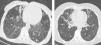

Thick wall cavities were significantly more common in the MDR group, whereas thin wall cavities slightly more common in the NTM group (Fig. 2). From another point of view, cavities of the MDR group mostly appear as cavitary consolidation while in the NTM group as cavities with satellite nodules, with significant difference between these two groups (Fig. 3). Multiple cavities in the NTM group have more homogenous lobar distribution whereas in the MDR group cavities were significantly more common in the right upper lobe (RUL) than in the middle and inferior lobes. Also multiple cavities in RUL were notably more frequent in MDR group than NTM group.

It is told that multiple cavities are even more common in MDR-TB than in drug-sensitive TB: 40% in MDR-TB versus 11% in drug-sensitive TB according to a study.13 In this study multiple cavities were more common in MDR-TB, but neither statistically significant nor differentiating. This different result is probably caused by long delay of NTM species diagnosis and can manifest that multiple cavities can also be produced by NTM in case of chronic illness without any appropriate treatment. Anyway, it seems that shape and distribution of cavities are more differentiating and reliable factor because NTM causes thin wall cavities mostly with satellite nodules in the related segment, but MDR-TB cavities are mostly lying within pulmonary consolidation with thick walls.

Martinez et al. believe that due to slower progression of disease, cavities seen in NTM are smaller and have thinner wall in comparison with post-primary TB.14 Likewise similar study by Burrill et al. demonstrated that cavities found in post-primary TB usually happen in case of pulmonary consolidation and have irregular thick walls.11